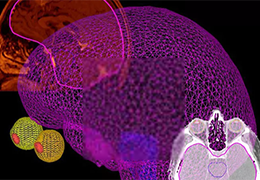

BrainVoyager is designed for high performance, ease of use and flexible data processing. BrainVoyager offers a comprehensive set of analysis and visualization tools which start their operation on raw data (2D structural and functional matrices) and produce beautiful visualizations of the obtained results.

Visualization Tools

Parametric and non-parametric statistical maps may be superimposed both on the original functional scans as well as onto T1-weighted 2D or 3D anatomical reference scans. Time courses of selected regions-of-interest (ROIs) are available both in 2D and 3D representations. Statistical maps may be computed either in the 2D or 3D representation since structural as well as functional 4D data (space x time) are transformed into Talairach space. This allows you to compare activated brain regions across different experiments and across different subjects

Segmentation

Segmentation of tissue (e.g., isolating the brain, differentiating gray and white matter) is performed using region-growing methods, filter operations as well as the application of 3D templates. Using the mouse it is very easy to explore a 3D volume with superimposed pseudocolor-coded statistical maps in a four-window representation showing a sagittal, coronal, transversal and oblique section. Based on a (segmented) 3D data set a three-dimensional reconstruction of the subjects' head and brain can be calculated and displayed from any specified viewpoint using volume or surface rendering.

Volume Rendering

Volume rendering is performed with a very fast ray casting algorithm; lightning calculations are based on Phong-shading. Surface rendering of reconstructed surfaces is performed using OpenGL. Using texture mapping, a reconstructed surface (e.g., head or brain) may be sliced in real time, showing both surface and volume data at the same time. Initial polygon meshes serve as the basis for surface finding, cortex inflation and cortex flattening computations.

Surface Reconstruction

The surface reconstruction procedure starts with a sphere (recursively tesselated icosahedron) or a rectangle, which slowly wraps around a (segmented) volume data set. In order to avoid topological defects and to let the surface smoothly grow into deep sulci, a dynamic mesh algorithm was developed which automatically invents new polygons on the fly at places where they are needed. A reconstructed cortical surface may be inflated, cut interactively and slowly unfolded minimizing areal distortions. Statistical 3D maps may be superimposed on reconstructed, inflated or flattened cortex. Signal time courses may be invoked by simply pointing to any region of a visualized surface.